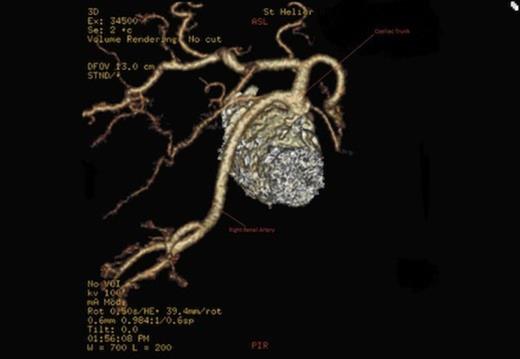

We present a rare case of an ectopic main right renal artery originating as part of the coeliac axis. Renal arteries are usually paired vessels which originate directly from the aorta to supply each kidney. Variations in their origin and numbers have been reported by many authors. However, there has only been one previous report of a left main renal artery arising from the coeliac axis in the medical literature, in 1980, seen during angiography. We believe we have the first CT angiographic evidence of such anatomy. This important aberrant anatomy must be noted not only for its rarity but also for its implications in the field of transplant surgery and interventional radiology. There will be more similar reports as non-invasive imaging is being used ever more frequently.

A CT scan revealed an aneurysmal distal thoracic aorta measuring 40mm and 49mm at the level of the diaphragm and of normal calibre at the left renal artery. The right renal artery very interestingly had its origin from the coeliac axis with no significant renal artery disease and the left renal artery showed calcific disease with post-stenotic dilatation at its ostium from the aorta. There were also no accessory renal vessels noted.

Therefore, we have only the second documented single main ectopic renal artery originating directly from the coeliac axis. Furthermore we are the only ones to have CT angiographic evidence of the above.